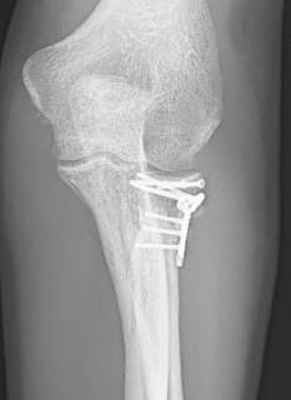

Лечение пациента с многооскольчатым переломом (Тип 3) после падения с горного велосипеда: Комбинированный остеосинтез с применением пластин с угловой стабильностью. Рентген показывает состояние сустава после заживления. © Gelenk Klinik

Даже сложные переломы с несколькими отломками и вывихами можно вылечить при помощи остеосинтеза. Для этого в Геленк Клинике используются специальные пластины с угловой стабильностью, которые надежно фиксируют отдельные фрагменты сустава